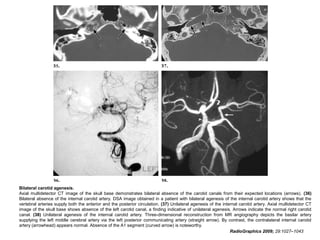

Internal Carotid Artery Agenesis

• Congenital absence of the internal carotid artery has a

prevalence of 0.01%.

• CT of the skull base and CT angiography in such cases

demonstrate an absence of the carotid canal.

• The anomaly may be unilateral or, more rarely, bilateral.

• The recognition of internal carotid artery agenesis is

important, especially in patients with cerebral

thromboembolic disease due to atherosclerosis of the

vertebrobasilar system.

• Poor collateral blood supply to the head places these

individuals at high risk during conventional angiography

and surgery.

• There is also a strong association between internal

carotid artery agenesis and the development of

intracranial aneurysms.

RadioGraphics 2009; 29:1027–1043

Bilateral carotid agenesis.

Axial multidetector CT image of the skull base demonstrates bilateral absence of the carotid canals from their expected locations (arrows). (36)

Bilateral absence of the internal carotid artery. DSA image obtained in a patient with bilateral agenesis of the internal carotid artery shows that the

vertebral arteries supply both the anterior and the posterior circulation. (37) Unilateral agenesis of the internal carotid artery. Axial multidetector CT

image of the skull base shows absence of the left carotid canal, a finding indicative of unilateral agenesis. Arrows indicate the normal right carotid

canal. (38) Unilateral agenesis of the internal carotid artery. Three-dimensional reconstruction from MR angiography depicts the basilar artery

supplying the left middle cerebral artery via the left posterior communicating artery (straight arrow). By contrast, the contralateral internal carotid

artery (arrowhead) appears normal. Absence of the A1 segment (curved arrow) is noteworthy.